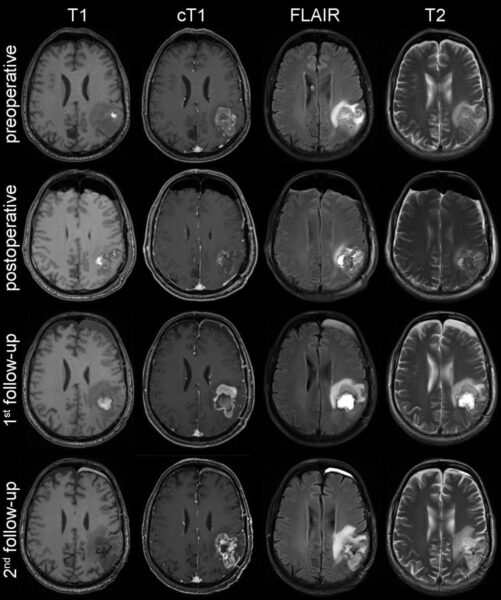

Anhand einer Referenzdatenbank mit MRT-Untersuchungen von knapp 500 Hirntumorpatienten des Universitätsklinikums Heidelberg erlernten die Algorithmen die Hirntumoren automatisch zu erkennen und zu lokalisieren. Außerdem konnten die Algorithmen die einzelnen Bereiche (kontrastmittelaufnehmender Tumoranteil, peritumorales Ödem) volumetrisch vermessen und das Therapieansprechen präzise beurteilen.

Die Ergebnisse des Forschungsprojekts wurden in Kooperation mit der European Organisation for Research and Treatment of Cancer (EORTC) umfassend validiert. „Die Auswertung von über 2.000 MRT-Untersuchungen von 534 Glioblastom-Patienten aus ganz Europa zeigt, dass unser computerbasierter Ansatz eine zuverlässigere Beurteilung des Therapieansprechens ermöglicht, als es mit der herkömmlichen Methode der manuellen Messung möglich wäre“, erklärt Philipp Kickingereder aus der Abteilung Neuroradiologie am Universitätsklinikum Heidelberg. „Wir konnten die Verlässlichkeit der Beurteilung um 36 Prozent verbessern. Das kann für die auf Bildgebung basierende Beurteilung der Wirksamkeit einer Therapie in klinischen Studien von entscheidender Bedeutung sein. Auch die Vorhersage des Gesamtüberlebens war mit unserem neuen Verfahren exakter möglich.“